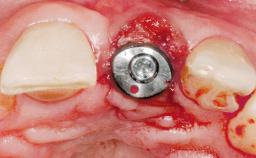

Immediate Flapless Placement of an Implant in a Maxillary Left Central Incisor Site

Pedro Tortamano, Luiz Otávio Alves Camargo

A 42-year-old female patient was referred to our clinic at the School of Dentistry of the University of São Paulo in November 2004, presenting a deficient restoration in the upper left central incisor. The clinical examination revealed no gingival retraction or any signs of gingival inflammation and, therefore, previous periodontal treatment was not considered. The patient presented a high lip line at full smile and a thin tissue biotype. This combination characterized a high-risk situation from an anatomic point of view, which required careful preoperative planning and cautious surgical execution.

Placement Protocol Immediate implant placement

Socket Morphology Single-root socket

Socket Integrity Sufficient, with intact bone walls